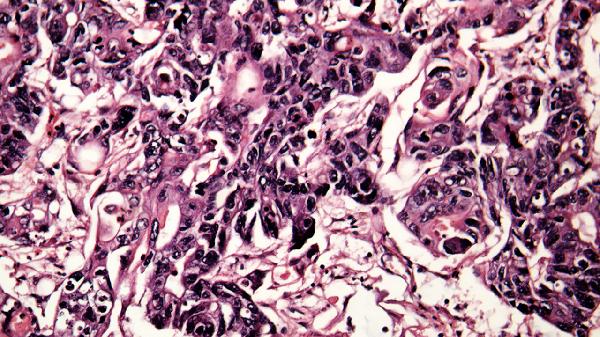

5、出血倾向

疾病后期可能出现皮下瘀斑、鼻出血、牙龈出血、呕血、便血等出血表现,与凝血功能障碍有关。严重者可发生内脏出血或脑出血。任何出血症状都提示病情危重,需紧急医疗干预。